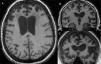

Dementia is a syndrome characterised by chronic, multi-domain, acquired cognitive impairment that causes significant functional limitations. MRI is the standard imaging study for these cases, since it enables detection of the atrophy patterns of the various neurodegenerative diseases (Alzheimer's disease, frontotemporal degeneration, Lewy body dementia), the vascular lesions associated with vascular dementia, and various potentially reversible diseases (for example, tumours, hydrocephaly) or diseases that require special management measures (for example, prion diseases). In certain cases other imaging methods can be used, such as CT, functional MRI, HMPAO SPECT or dopaminergic markers and FDG PET, amyloid markers or dopaminergic markers. The indications for these methods have not yet been clearly established, and therefore should be used in multidisciplinary dementia units.